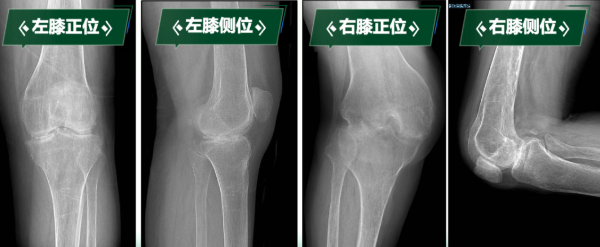

• 一條腿僵硬如棍 一條腿屈曲90° 如何破除“僵直”枷鎖

“真不敢相信,我能站起來,還能走路……”劉阿姨因罹患類風(fēng)濕性關(guān)節(jié)炎多年,骨質(zhì)受到嚴(yán)重侵蝕,導(dǎo)致雙膝關(guān)節(jié)逐漸纖維性強(qiáng)直,更加棘手的是,雙膝強(qiáng)直于兩個極端體位,左膝關(guān)節(jié)無法彎曲,像“木棍”一樣始終處于伸直狀態(tài);右膝長